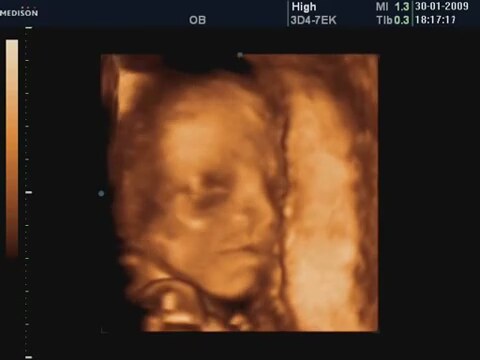

21 Haftalık Bebeğin 4 Boyutlu Ultrasın Görüntüsü